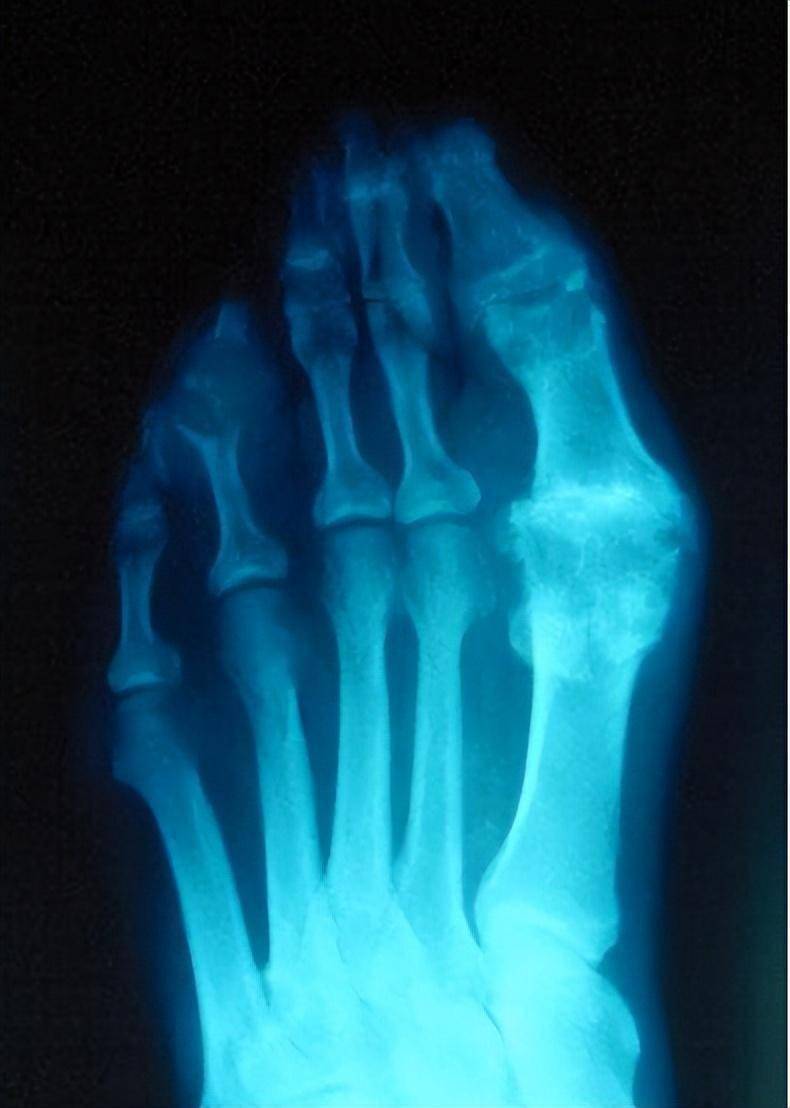

段如仁的x光片显示,其左脚大拇指处痛风石较为严重

痛风x线表现

痛风影像表现

痛风有哪些影像表现